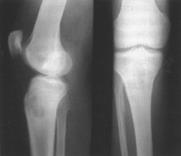

Захворювання починаєть­ся в молодому віці і може себе прояви­ти через багато років. Пацієнти скаржать­ся на ниючий біль у кінцівці, який по­силюється вночі або під час фізичного навантаження, локальну болючість під час постукування по ураженій ділянці. Діагноз ставлять на підставі рентгено­логічних даних. У кістці виявляється круглої форми різних розмірів порож­нина з чіткими контурами. По краях порожнини є склеротична облямівка. Температурна реакція відсутня. Ліку­вання оперативне: розкриття порож­нини абсцесу, вишкрібання її, проми­вання антибіотиками і тампонада м’я­зовим клаптем на ніжці.

Склерозуючий остео­мієліт Гарре (osteomyelitis scleroticans Garre). При цій формі запалення кістки в ній перева­жають остеосклеротичні процеси з по­ступовим запустінням кістково-мозкового каналу. Захворювання теж пере­бігає торпідно, тривало, з невираженою клінічною картиною: незначний нічний біль у кінцівці, біль під час фізичного навантаження, потовщення кінцівки, локальна болючість під час пальпації. Температура тіла помірно підвищена. Запальний процес ушкод­жує переважно діафізи. Діагноз став­лять на підставі рентгенологічних даних: веретеноподібне потовщення діафі­за кістки, на тлі якого можуть бути помітні невеликі порожнини з дрібни­ми секвестрами. Рідко захворювання починається гостро, з підвищення тем­ператури тіла й інтоксикації. Явища ці швидко минають, і процес набуває хронічного перебігу.

Альбумінозний остео­мієліт Ольє (osteomyelitis albuminosa Oilier) спостері­гається рідше, ніж інші види остео­мієліту. Для нього характерне субкортикальне і субперіостальне утворення порожнин, заповнених слизовим, білковим або маслянистим ексудатом. Іноді є дрібні секвестри. Частіше уш­коджуються стегнова і плечова кістки. Початок захворювання прихований, перебіг млявий. Хворі скаржаться на біль в ураженій кінцівці. Процес зви­чайно локалізується в дистальному відділі стегнової кістки. До болю при­єднується припухлість, яка поступово наростає. На рентгенограмі в кістці видно правильної і неправильної форми порожнисті утвори з періостальними нашаруваннями.